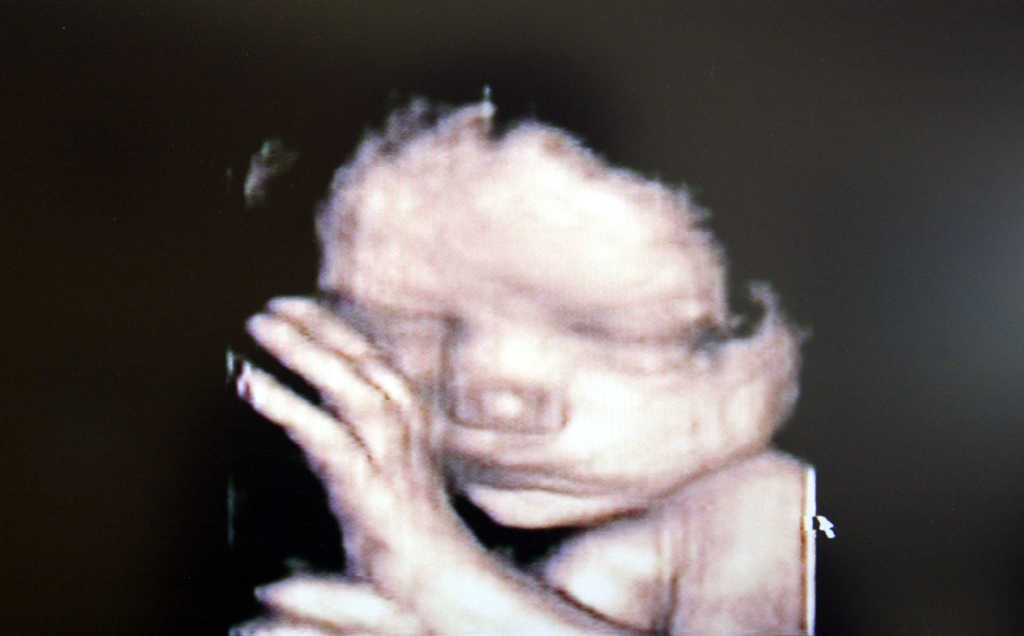

The measure indicates that “a fertilized egg, embryo, or fetus may not be understood to have independent rights under any of the laws of this State.”

He added, “It is a very, very sad time in the history of our state that something so horrifying can even be written on paper, never mind considered as law. What has happened to us? Why does anyone think killing a baby in the womb is a good thing, never mind insisting that society pay for it, allowing it when the child can clearly feel horrific pain, endangering the health of women and hurting society as a whole?”